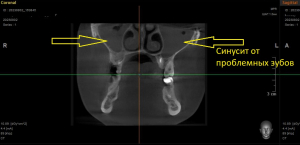

В нашу клинику обратилась пациентка, которая длительно и безуспешно пыталась вылечить хронический синусит верхнечелюстной пазухи(гайморит).

Ранее пациентка консультировалась у ЛОР-специалиста и нескольких стоматологов из других клиник- пациентке был предложен единственный вариант лечения, связанный с удалением двух проблемных зубов с воспалительным процессом на верхней челюсти , плюс проведение консервативного ЛОР лечения. Пациентка с вариантом удаления двух зубов не согласилась и обратилась к нам в клинику. После проведения диагностических мероприятий было установлено наличие обширных воспалительных процессов на двух зубах на верхней челюсти, а также на нижнем зубе.

Нами было проведено повторное эндодонтическое лечение проблемных зубов.Через 6 месяцев видны отличные результаты заживления воспалительных изменений на верхушках корней, а также устранение воспаления в верхнечелюстной пазухе( гайморита).